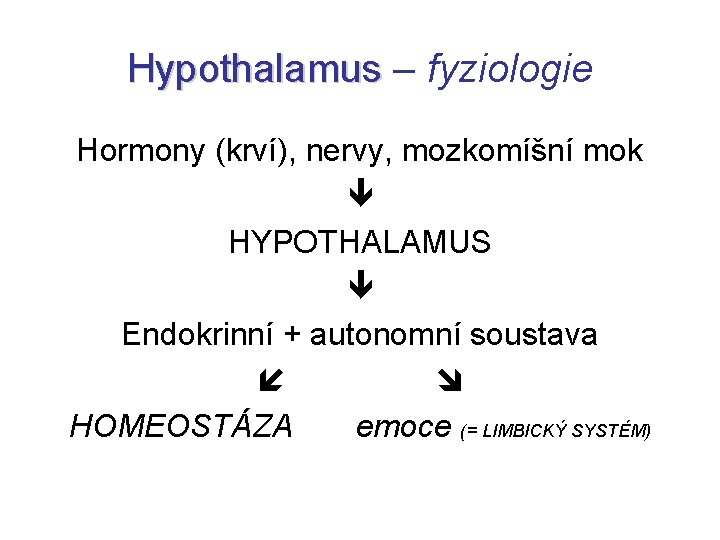

Hypothalamus – fyziologie Hormony (krví), nervy, mozkomíšní mok HYPOTHALAMUS Endokrinní + autonomní soustava HOMEOSTÁZA emoce (= LIMBICKÝ SYSTÉM)